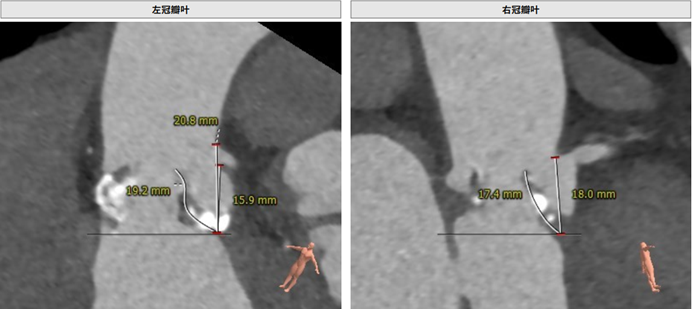

左冠瓣叶长度:19.2 mm,右冠瓣叶长度:17.4 mm

左冠开口高度:16.4 mm;右冠开口高度:15.6 mm

钙化积分:606 mm³,重度钙化

由于患者瓣叶增厚且稍长,法式窦结构偏小,术者团队认为术中可能存在发生双侧冠脉阻塞的风险。结合患者主动脉根部情况及病情等综合因素,吴连拼院长在组织科室集体对患者病变进行深入分析和多次讨论后决定通过球囊预扩后予以进一步确认,必要时行冠脉保护。选用22 mm球囊预扩张。